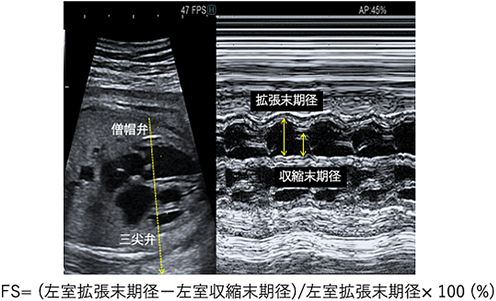

心室内径短縮率(fractional shortening: FS):胎児心臓の収縮能としてMモードを用いて四腔断面で房室弁付着部直下にカーソルを設定し心室壁の動きを記録し,心室内腔の拡張末期径と収縮末期径の差を拡張末期径で除することで計算される心室内径短縮率(fractional shortening: FS; Fig. 3)がある.正常値は0.28~0.40で,妊娠後期に軽度減少するという報告8)と週数によらず一定であるとする報告9)がある.

Pediatric Cardiology and Cardiac Surgery 40(2): 103-112 (2024)

Fig. 3 心室内径短縮率 (fractional shortening: FS)